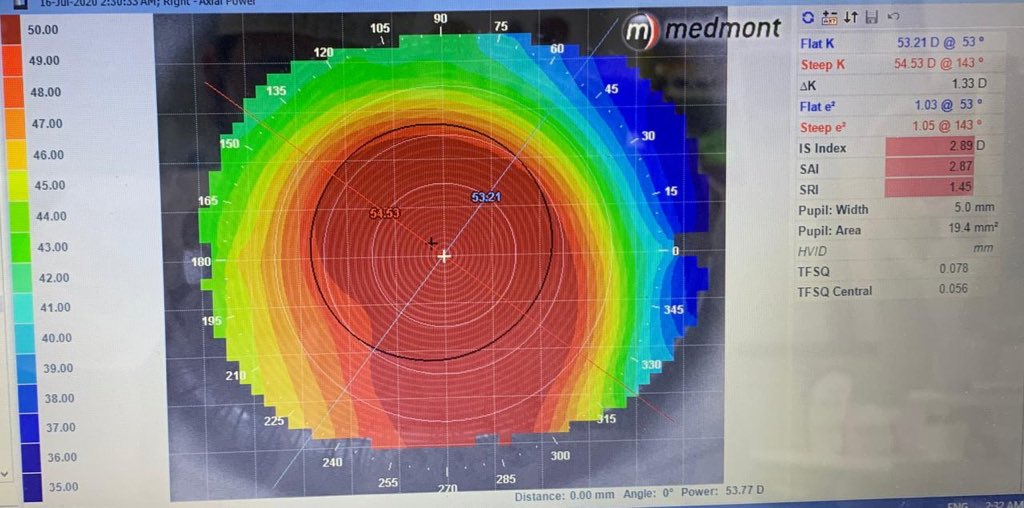

عمر المريض 32 سنه ، زار العياده قبل 4 سنوات ، معه قرنيه مخروطيه متقدمه ولكن من النوع الي نسميه Keratoglobus اي ان القرنيه محدبه ومخروطيه ولكن بشكل منتظم ، ينتج عنه قصر نظر شديد وانحراف قليل عكس حالات القرنيه المخروطيه التقليديه حيث يزيد الانحراف عن القصر في معظم الاحيان !!

في زيارته الاولى قبل 4 سنوات ، كان يستخدم عدسات لينه تقليديه قوتها تقريبا -10.00 درجات ، طبعا كونها اصلا غير ملائمه لسطح القرنيه المحدب كانت تتحرك كثير وتسبب جفاف والم واحمرار وكراهيه شديده للضوء ولكن كان يتحمل كل هالمعاناه لانها تعطيه نظر يقدر يمشي حاله فيه !!